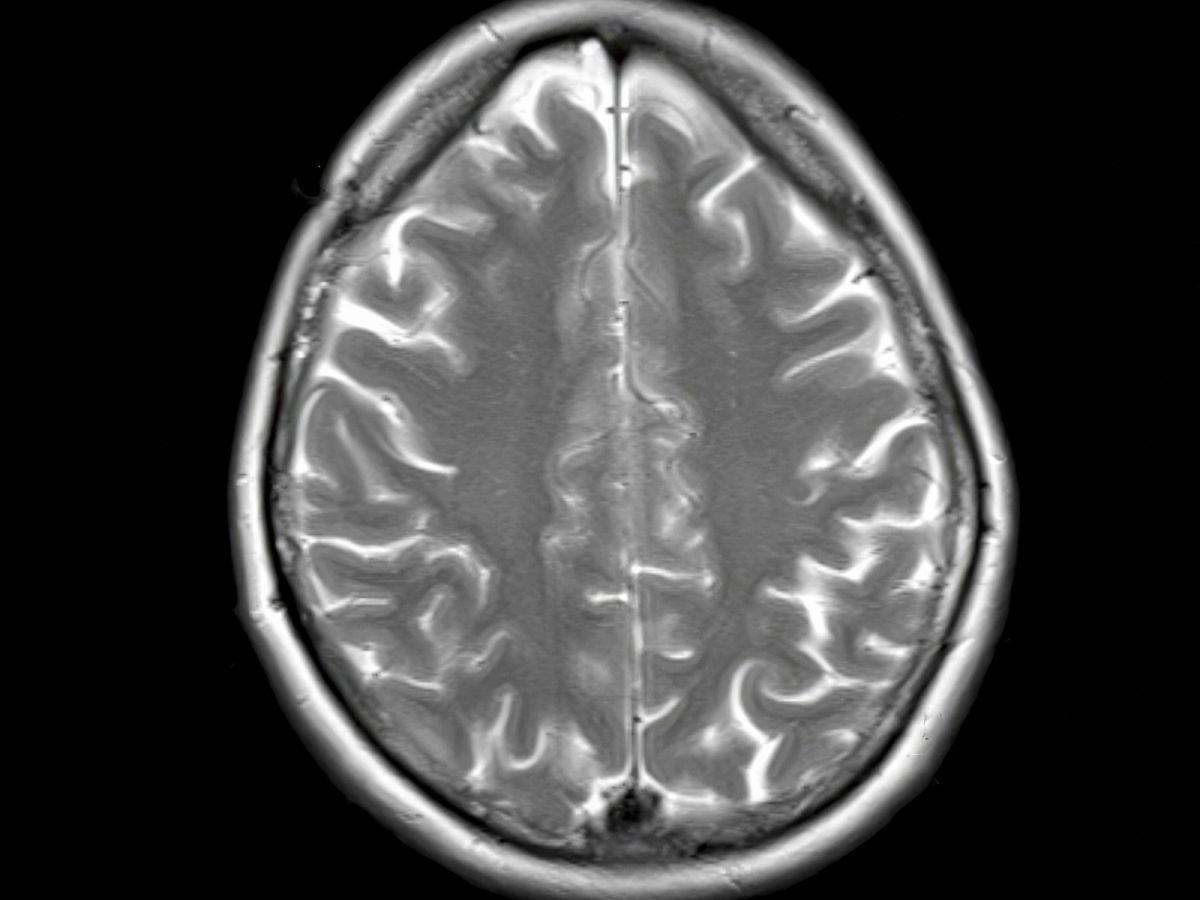

Hypertrophiée chez notre espèce par rapport aux autres primates, cette écorce entourant le cerveau fonctionne comme une interface entre nos perceptions et notre capacité à choisir et à agir.